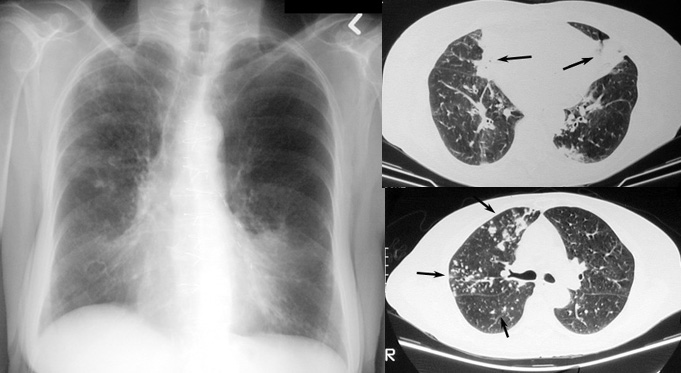

Информация о диссеминированном рассеянном энцефаломиелите